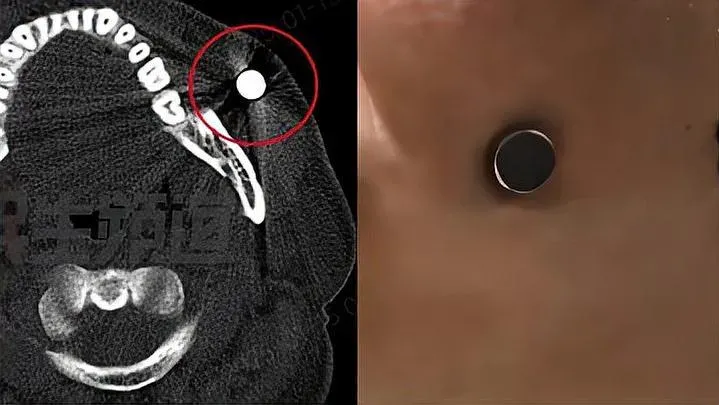

• 男子面腫4日竟「磁力王上身」吸實磁鐵!醫生驚訝20年來首見

男子面腫4日竟「磁力王上身」吸實磁鐵!醫生驚訝20年來首見